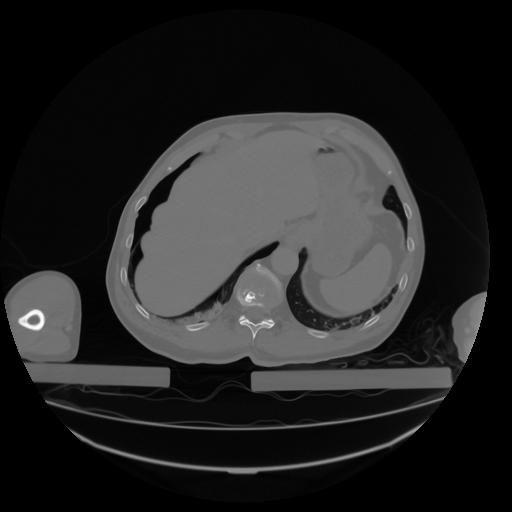

27 CUERPO,CE,Axial,3.0,CUERPO,,